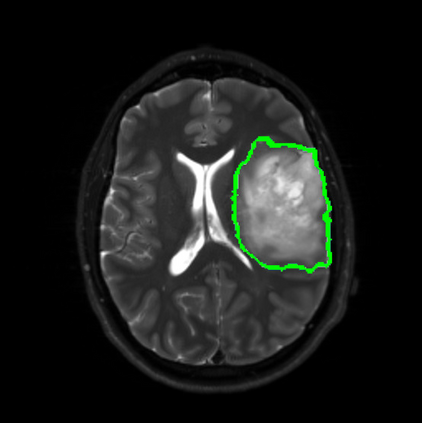

Radiomics uses quantitative medical imaging features to predict clinical outcomes. Currently, in a new clinical application, finding the optimal radiomics method out of the wide range of available options has to be done manually through a heuristic trial-and-error process. In this study we propose a framework for automatically optimizing the construction of radiomics workflows per application. To this end, we formulate radiomics as a modular workflow and include a large collection of common algorithms for each component. To optimize the workflow per application, we employ automated machine learning using a random search and ensembling. We evaluate our method in twelve different clinical applications, resulting in the following area under the curves: 1) liposarcoma (0.83); 2) desmoid-type fibromatosis (0.82); 3) primary liver tumors (0.80); 4) gastrointestinal stromal tumors (0.77); 5) colorectal liver metastases (0.61); 6) melanoma metastases (0.45); 7) hepatocellular carcinoma (0.75); 8) mesenteric fibrosis (0.80); 9) prostate cancer (0.72); 10) glioma (0.71); 11) Alzheimer's disease (0.87); and 12) head and neck cancer (0.84). We show that our framework has a competitive performance compared human experts, outperforms a radiomics baseline, and performs similar or superior to Bayesian optimization and more advanced ensemble approaches. Concluding, our method fully automatically optimizes the construction of radiomics workflows, thereby streamlining the search for radiomics biomarkers in new applications. To facilitate reproducibility and future research, we publicly release six datasets, the software implementation of our framework, and the code to reproduce this study.

翻译:放射科使用定量医学成像特征来预测临床结果。目前,在一个新的临床应用中,通过一个超常试验和高压过程,通过人工操作,从广泛的现有选项中找到最佳放射法。在本研究中,我们提议了一个框架,自动优化每个应用程序的放射工作流程的建设。为此,我们将放射作为模块工作流程,并包括每个部件的大量通用算法。为了优化每个应用程序的工作流程,我们使用随机搜索和聚合的自动机学习方法。我们用12种不同的临床应用来评估我们的方法,结果在曲线下应用的以下领域:1) 脂色瘤(0.83);2) 脱氧型纤维瘤(0.82);3 初级肝脏肿瘤(0.80);4 气肠肿瘤(0.77)、5 彩虹肝脏移植(0.61); 6 脑膜细胞变异常(0.45); 7) 肝细胞变异常(0.8) 脑纤维变异位(0.80); 9) 直径直线型癌症(0.74) 和头型癌症(0.77) 直径研究(10) 。